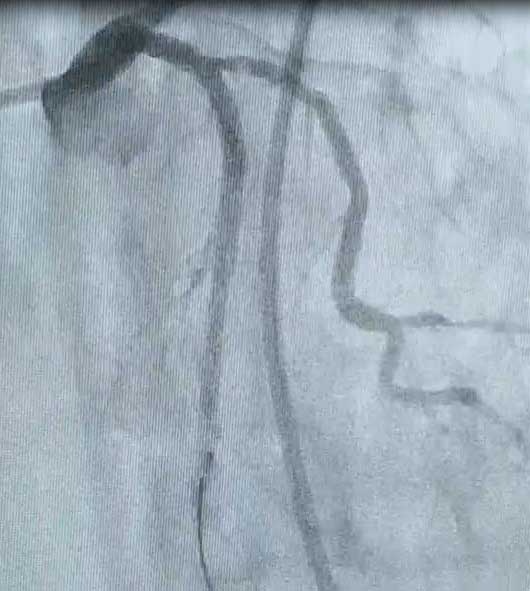

导管室迅速开放,紧急为患者做了冠脉造影,结果显示:前降支中段闭塞!开通前降支并植入支架2枚,患者前降支血流恢复,胸痛缓解,入住心内科CCU继续进行后续治疗。患者转危为安,一场与死神赛跑的生命争夺战以手术的成功完成而告终!